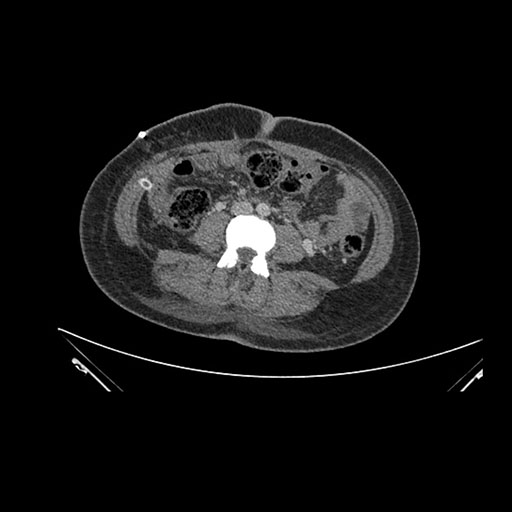

Imaging Analysis

Look through the patient's CT scan to identify any areas of concern for the necessary procedure.

Axial Arterial

Based on initial findings, which issue(s) would you be most concerned about?